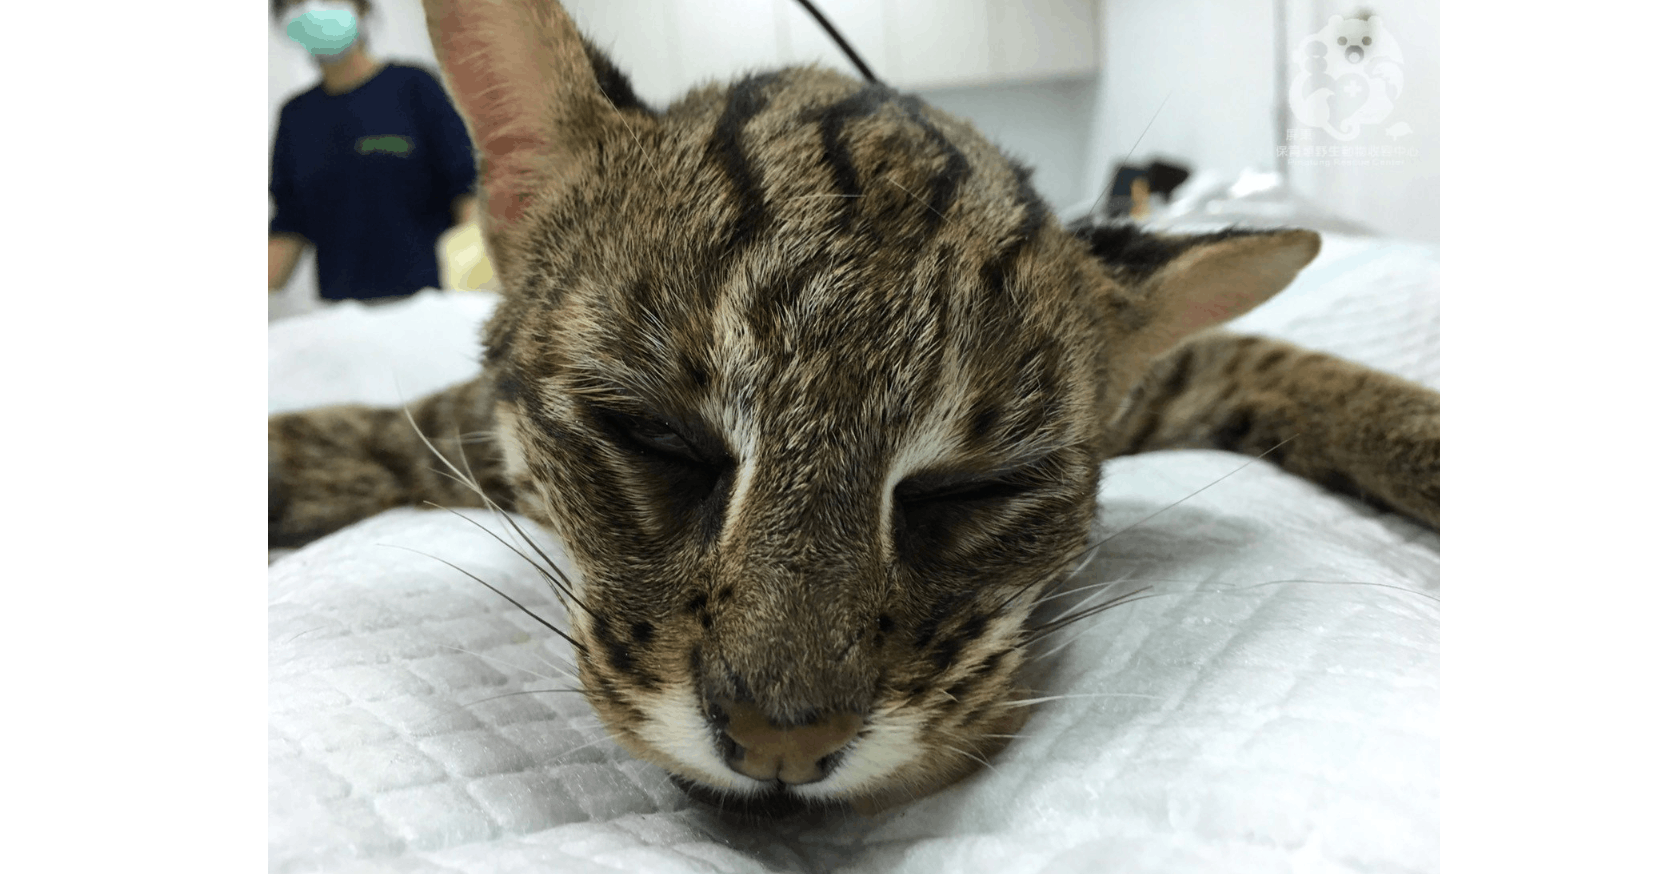

電腦斷層攝影(CT)利用X光穿透體內,再經由電腦重組呈現體內3D影像,實務上不是只有人類使用,屏東科技大學保育類野生動物收容中心與該校獸醫教學醫院合作進行了野生動物的拍攝。和在一般人在醫院的情況大大的不同,雖然畫面沒有拍到但因為是大工程動用人力不少,有紅毛猩猩、馬來熊、老虎、花豹(?)…等,乖乖的躺在床上其實還滿可愛的。

電腦斷層攝影(CT)利用X光穿透體內,再經由電腦重組呈現體內3D影像,實務上不是只有人類使用,屏東科技大學保育類野生動物收容中心與該校獸醫教學醫院合作進行了野生動物的拍攝。和在一般人在醫院的情況大大的不同,雖然畫面沒有拍到但因為是大工程動用人力不少,有紅毛猩猩、馬來熊、老虎、花豹(?)…等,乖乖的躺在床上其實還滿可愛的。